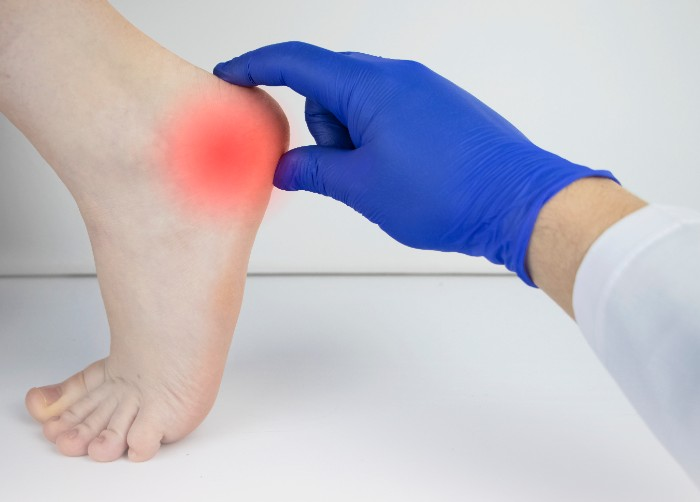

Muitas vezes, o que a gente precisa é de uma orientação profissional para entender o que está acontecendo e qual o melhor caminho para tratar a dor no calcanhar por esporão. Um médico, como um ortopedista, pode fazer o diagnóstico correto e indicar o tratamento mais adequado para você. E não se preocupe, geralmente não é nada complicado.

Dica Prática: Se a dor for muito intensa e persistente, procure um médico ortopedista. Ele poderá solicitar exames, como um raio-X, para confirmar o esporão e indicar o tratamento ideal, que pode incluir fisioterapia e o uso de palmilhas específicas.